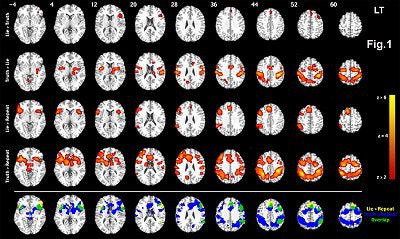

In another study, Dr. Daniel Langleben, an assistant professor of psychiatry at the University of Pennsylvania in Philadelphia, showed that deception is distinguishable from truth by increased prefrontal and parietal activity, and that fMRI clearly revealed frontal lobe activity associated with lying (Human Brain Mapping, December 2005, Vol. 26:4, pp. 262-272).

![]() |

| Group analysis showing significant differences in brain activation between Lie, Truth, and Repeat Distracter conditions. Row 1: Truth > Repeat Distracter; row 2: Lie > Repeat Distracter; row 3: Lie > Truth (blue scale) Truth > Lie (red scale). Images are displayed over a Talairach-normalized template in radiological convention. Significance thresholds for all contrasts based on spatial extent using a height of z ≥ 2.57 and cluster probability p ≤ 0.05, except Lie > Truth (blue scale) presented at a z ≥ 1.64, uncorrected. Image courtesy of Dr. Daniel Langleben. |

Could defense attorneys start ordering MRI exams as "proof" that their clients are telling the truth when they claim they suffered from diminished mental capacity at the time of the crime and did not understand their actions?

Possibly. According to Langleben, the No Lie MRI system, when used in combination with a carefully controlled query procedure, demonstrated 80% to 92% accuracy versus a polygraph test, which turns in an accuracy of 50% to 90%.

"The problem with polygraph is that it seems to be operator-dependent and thus susceptible to manipulations," Langleben told AuntMinnie.com. With the 3-tesla MR test, "no one 'reads' the scan," he said. "The data is automatically processed with preset thresholds of significance."